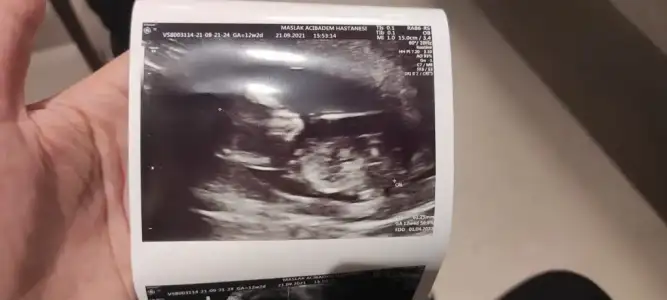

Bana da bakabilir misin ? 12+2

Bir tahmininiz var mı ?